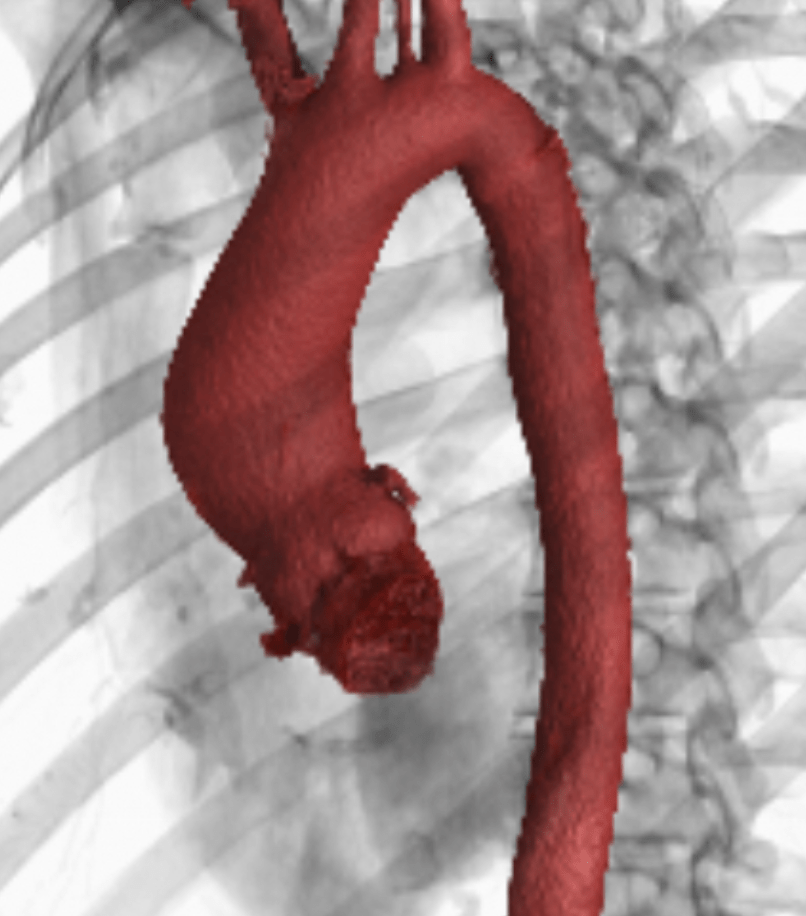

And in addition to my valve, I also have dilation of my aorta (below is the CT rendering of my actual aorta…pretty cool to see!):